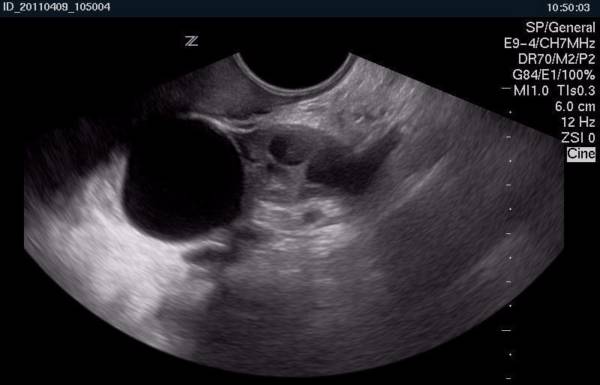

- УЗИ, КТ, МРТ;